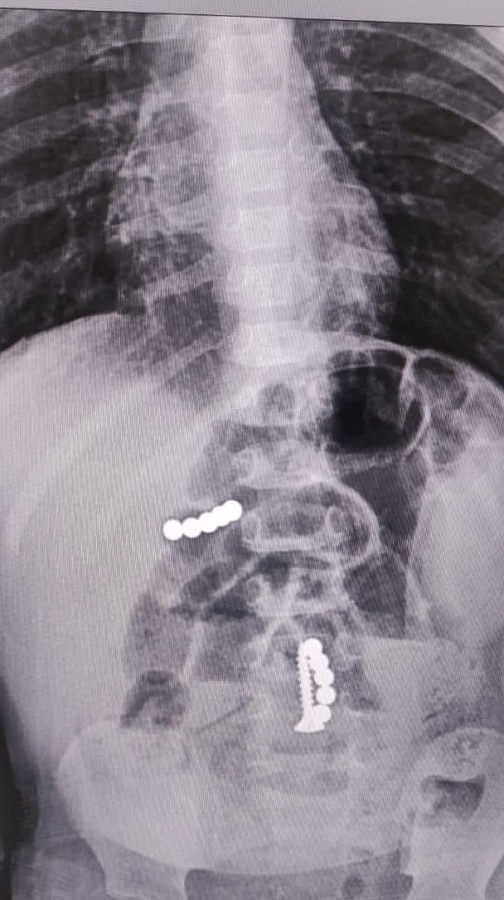

Несмотря на отсутствие прямых признаков хирургического заболевания, дежурным врачом хирургом была назначена рентгенография брюшной и грудной полости. Так, благодаря обследованию были выявлены множественные инородные тела желудочно-кишечного тракта – магниты и саморез.

Ребёнку экстренно выполнена фиброгастродуоденоскопия. Два магнита диаметром по 5 мм были удалены из полости желудка. Врачи обнаружили, что в толще стенки определяется еще один магнит. Было решено не удалять его, так как существовал риск травматизации полого органа. После необходимой подготовки ребёнок взят в операционную на лапаротомию.

В результате оперативного вмешательства врачи удалили 3-й магнит без повреждения задней стенки желудка. При дальнейшей ревизии установлено изменение тонкой кишки за счет наличия инородных тел в просвете кишечной трубки, с несколькими перфоративными отверстиями. Через дефекты кишечной стенки удалены инородные тела хирурги вытащили 1 саморез, 5 магнитных шариков. В месте наибольшего изменения кишечной стенки подвздошной кишки после устранения заворота произведена резекция.